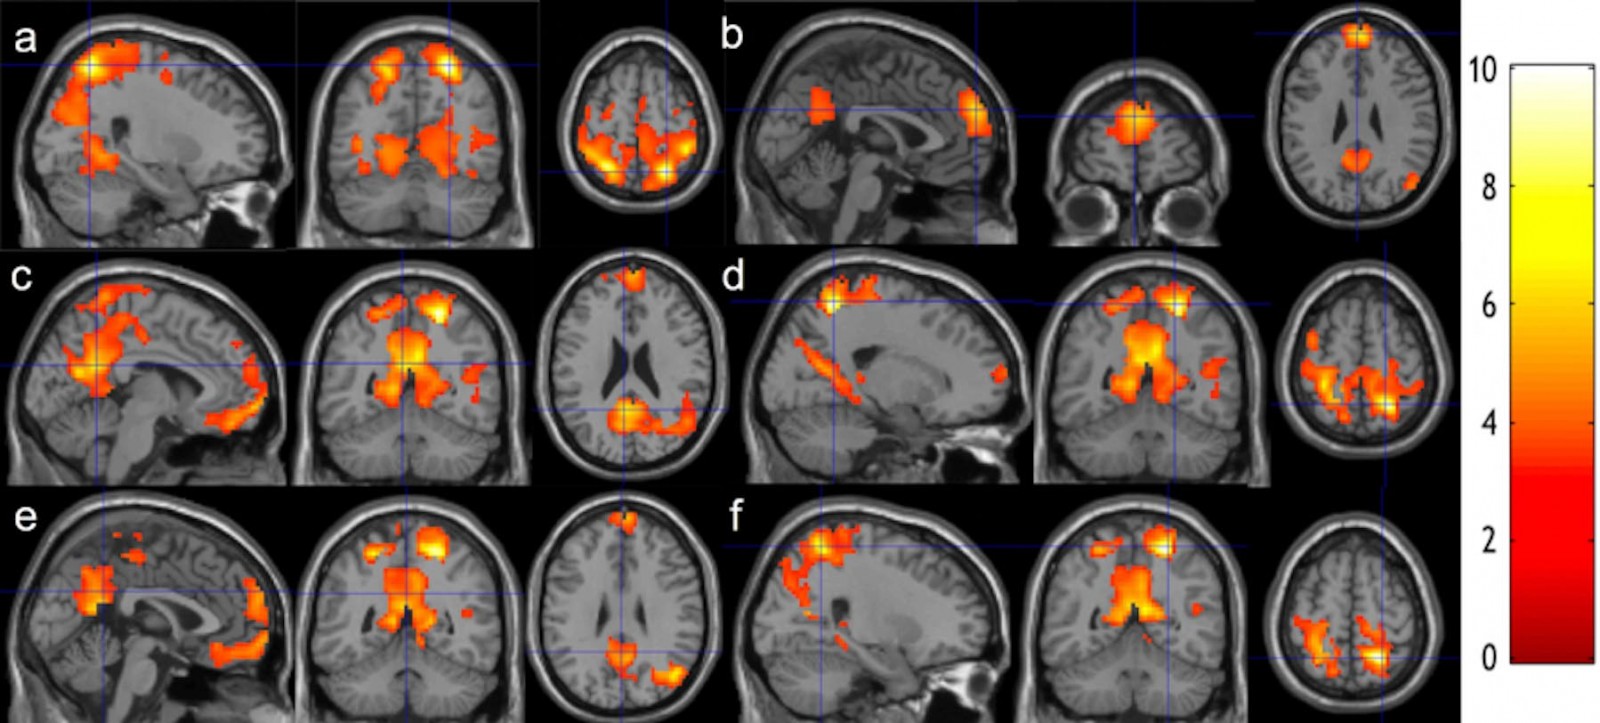

The evidence comes from an international study conducted at the University of Montreal and Italy's National Research Council that examined Buddhist monks from the Thai Forest Tradition using cutting-edge brain imaging technology. The results published in Neuroscience of Consciousness reveal something remarkable: meditation isn't a passive mental state. It's one of the most cognitively demanding activities your brain can perform.

The scientists used magnetoencephalography (MEG), a neuroimaging technology that records the brain's electrical signals with extraordinary precision. Unlike f MRI, which shows blood flow changes and has a slower temporal resolution, MEG captures the brain's electromagnetic activity in real time, millisecond by millisecond. This matters because meditation involves rapid, dynamic changes in neural activity. You need to see what's happening moment to moment, not just overall patterns.

The data wasn't just raw brain signals. Researchers used advanced signal analysis and machine learning algorithms to extract multiple indicators of neural complexity and dynamics. They measured neural oscillations (rhythmic patterns of electrical activity), signal complexity (how information-rich the neural activity was), and criticality parameters (how close the brain operated to the optimal balance point between order and chaos).

The study examined two classical meditation techniques that produce distinct experiences and, as it turns out, distinct brain states.

Samatha meditation is concentration practice. You pick an object of focus—often the breath—and you narrow your attention onto it completely. Everything else falls away. Your field of awareness becomes narrow, intense, and unwavering. Karim Jerbi, a study coauthor and psychology professor at the University of Montreal, compares it to narrowing the beam of a flashlight. You're not trying to see the whole room. You're trying to see one point with absolute clarity.

The neurological signature of Samatha is increased stability and focus. The brain shows heightened synchronization in networks associated with attention. Neural oscillations become more organized. The overall effect is a brain in a highly concentrated state, moving toward greater order and stability.

Vipassana meditation is insight practice. Instead of focusing on one point, you open your awareness to everything. You observe thoughts, sensations, and emotions as they arise without judgment, without trying to control them, without letting them carry you away. It's more dynamic, more expansive, more complex.

Jerbi describes Vipassana like widening the flashlight beam. You're not focusing on one point anymore. You're taking in the whole landscape. You're noticing everything, reacting to nothing, observing the entire field of your mental experience.

The brain during Vipassana shows different patterns. There's less synchronized focus, more distributed activity across multiple networks. The brain becomes more flexible, more adaptive, more responsive to shifting mental phenomena. In a real sense, the brain is engaged in more complex information processing because it's handling a wider range of inputs simultaneously.

Here's where it gets interesting: the study found that both practices increased the overall complexity of brain signals compared to rest. But they achieved this complexity through different mechanisms.

With Samatha, you get high-complexity brain activity through deep, focused, organized engagement with a single object. Think of it as intensive complexity. The brain is running at maximum intensity within a narrow channel.

With Vipassana, you get high-complexity brain activity through distributed, open-awareness engagement with multiple phenomena. Think of it as extensive complexity. The brain is running at high intensity across a wide field.

The critical finding: only Vipassana consistently moved the brain closer to the optimal critical state. This suggests that open-awareness meditation might produce superior long-term neurological benefits compared to focused attention alone. But this doesn't mean Samatha is inferior. They're tools for different purposes. Samatha builds concentration capacity. Vipassana builds flexibility and insight.

Remember that the study looked at the criticality deviation coefficient, a specific measure of how far the brain's neural dynamics deviate from the critical point.

This is where Samatha and Vipassana showed their clearest distinction.

During Samatha, the brain moved toward greater order and stability. The criticality coefficient shifted, reflecting a brain operating in a more stable, less flexible configuration. This makes sense for focused attention meditation. Your goal is to narrow your awareness, stabilize your attention, and exclude distractions. Your brain reorganizes to achieve exactly that.

During Vipassana, the brain moved closer to the critical point itself. Rather than moving toward order, it moved toward the balance point between order and chaos. This also makes sense for open-awareness meditation. Your goal is to maintain clear perception of whatever arises, which requires flexibility, adaptability, and the capacity to respond to unpredictable mental phenomena.